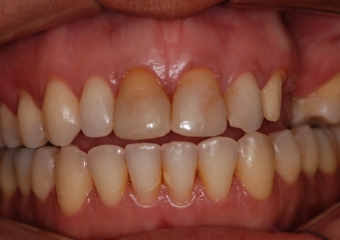

Imagens iniciais observando importante perda óssea e dentária superior